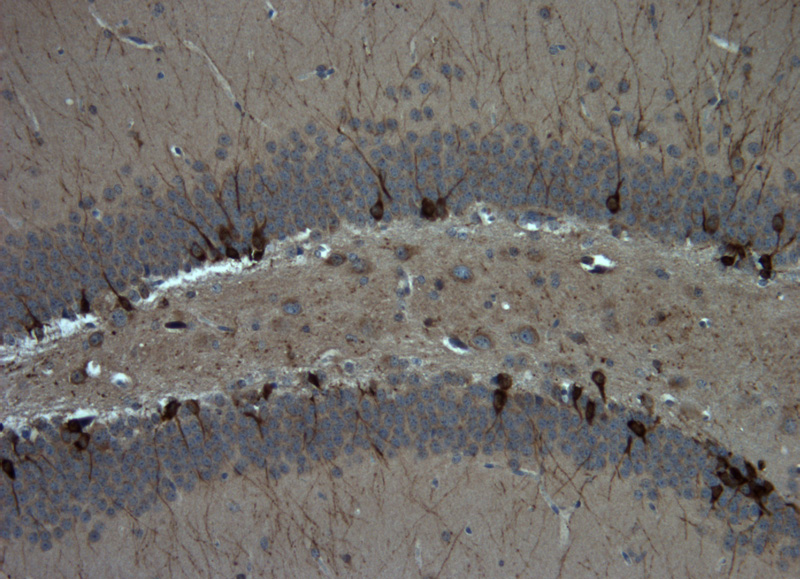

Our unit currently comprises the housing room and some laboratories of the Pharmacology department where we are able to conduct projects involving a limited number of animals (rats and mice). One of the laboratories is used for in vivo models, with two stereotaxic units for brain surgery procedures; the other laboratory has microtome and cryostat equipment for cutting histological sections which are used for all the colorimetric, immunofluorescence and immunohistochemistry assays, cell degeneration assays, and in situ hybridisation for detecting levels of expression of specific mRNAs. After histological sections have been viewed under the microscope, the images can be analysed. We also have a laboratory equipped for performing implantation surgery of brain dialysis probes (mice and rats) and for obtaining samples from freely-moving animals; a further laboratory is used for assaying neurotransmitters and/or substances derived from brain dialysate.

• protein expression of specific antigens through immunohistochemical and immunofluorescence assays on cell cultures, primary cultures and histological sections;

AF-IH Immunohistochemistry of an antigen on histological sections or on primary cultures: 10 slides (favourable rates can be arranged according to the number of samples to be examined and slides required) 280.00 + cost of antibody

AF-IF Immunofluorescence of an antigen on histological sections or on primary cultures: 10 slides (favourable rates can be arranged according to the number of samples to be examined and slides required) 280.00 + cost of antibody